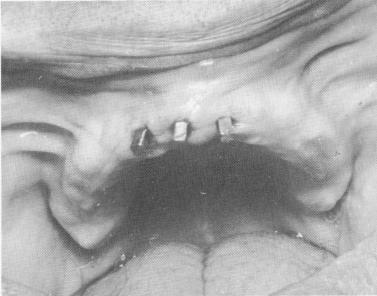

Fig. 10-234. A scalloped template is fabricated. It should include a posterior palatal connecting bar and vertical mush-room pin heads with predetermined holes through the template. It should also include a number of pontics for the support of the superstructure. The peripheral borders should be rounded so as not to injure the soft tissue. It should have a polished undersurface.

4 Template with palatal connecting bar & vertical mushroom pin heads